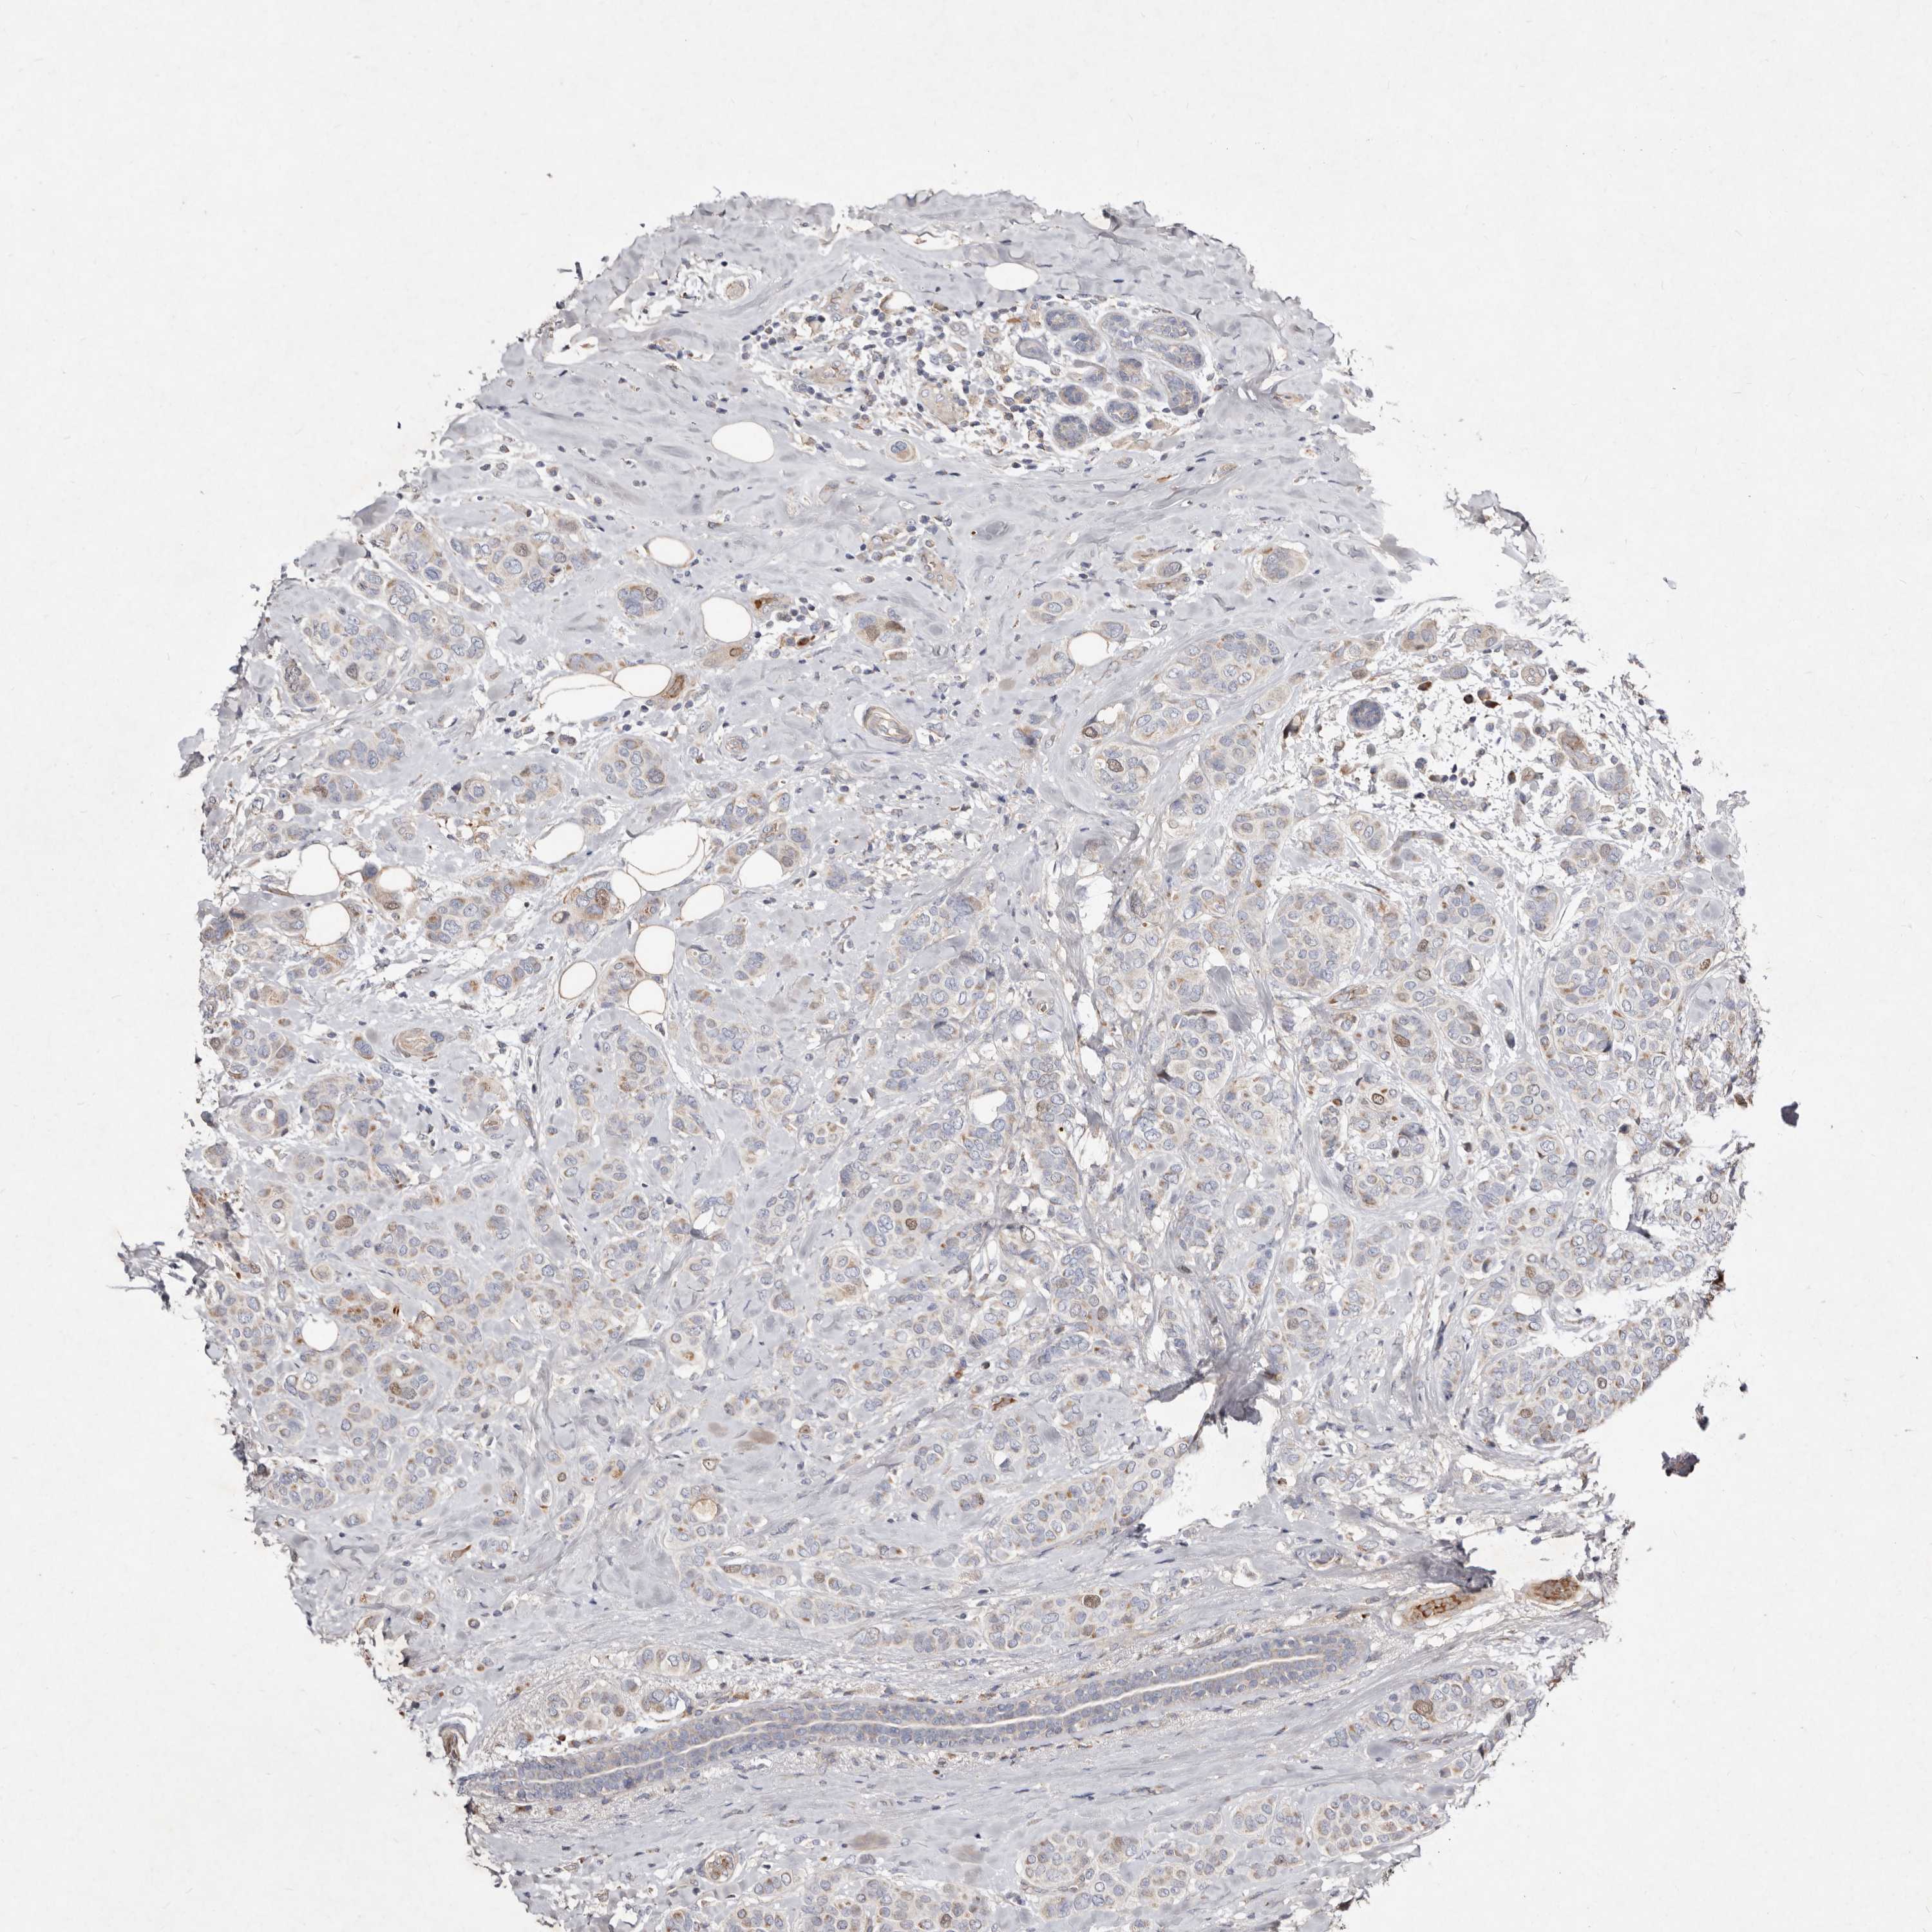

CANCER BREAST CANCER Show tissue menu

BRCA TCGA BRCA VALIDATION PROTEIN EXPRESSION